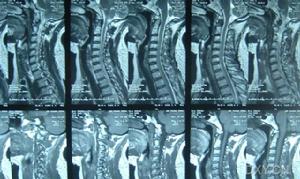

先天性肌斜頸--CT由於一側胸鎖乳突肌緊張,患有小兒肌性斜頸的孩子頭部會傾向患側,而臉面則會轉向健側(即沒有發生病變的一側)。如果不及時就診,孩子半歲到一歲時,會造成眼睛斜視,患側臉面、眼睛變小,面部不對稱,嚴重的還可能產生繼發性的胸椎側凸畸形。